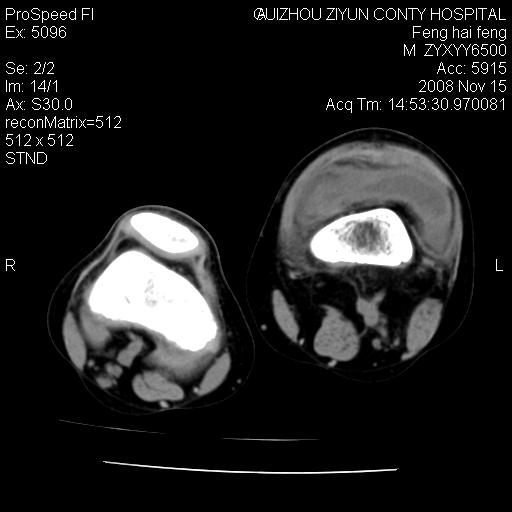

标题: CT16656:M 14Y 左膝关节肿胀一年余。其余病史不详。 [打印本页]

标题: CT16656:M 14Y 左膝关节肿胀一年余。其余病史不详。

考虑左侧髌骨结核;左膝关节滑膜肿胀、增厚,关节囊积液。

左膝滑膜型关节结核可能性大!支持!滑膜型关节结核主要ct表现:关节囊肿胀,积液,关节面见小破坏灶,并见点状死骨!

好大的左腿!考虑左侧髌骨结核,左膝关节滑膜肿胀、增厚,关节囊积液。

左侧髌骨结核;左膝关节滑膜肿胀、增厚,关节囊积液